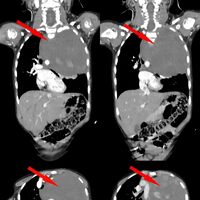

Родители показали дочь врачам, когда заметили у нее небольшую припухлость в области шеи. Специалисты по месту жительства выявили огромное новообразование размером со страусиное яйцо, которое сдавливало сердце и легкое. Сквозь ткань опухоли проходили крупные сосуды: «позвоночная артерия, питающая головной мозг, и подключичная артерия с ее ветвями, питающая левую руку». После телемедицинской консультации ребенка направили в Москву.

«По результатам контрольного гистологического исследования всего объема опухоли были обнаружены злокачественные клетки и установлен точный диагноз — ганглионейробластома», — поделились в пресс-службе.